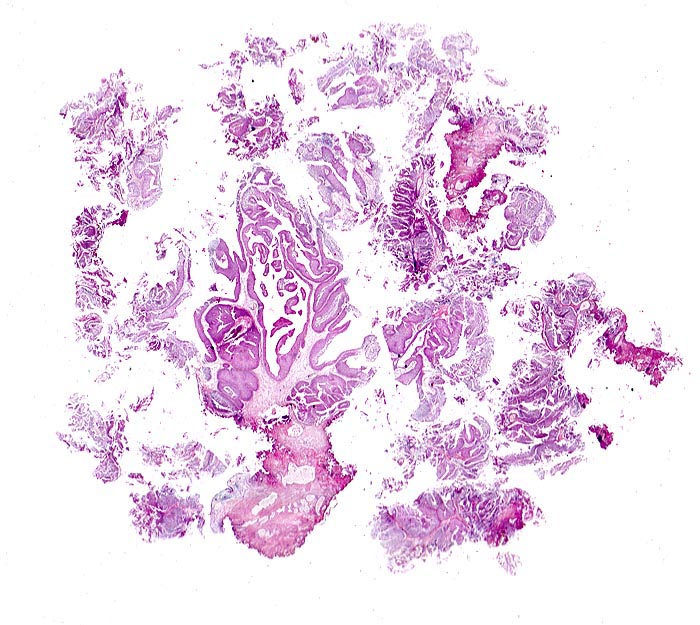

PathoPic – image database / PathoPic ID 4882 - Nicht invasives papilläres Urothelkarzinom pTa

Nicht invasives papilläres Urothelkarzinom pTa

Material einer transurethralen Resektion (TUR-B): multiple Fragmente eines papillären Tumors. Die fibrovaskulären Stromastiele werden von einem verbreiterten Urothel bedeckt. Die Grenzen zwischen Urothel und Stroma sind scharf und sprechen gegen ein invasives Tumorwachstum. Die Beurteilung einer möglichen Stromainvasion muss jedoch in einer stärkeren Vergrösserung erfolgen.

Die zystoskopische Abklärung einer Makrohämaturie ergab einen papillären Tumor an der Blasenhinterwand. Der Tumor wird transurethral reseziert.